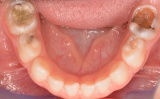

Σε ορισμένες περιπτώσεις πολύ χαλασμένων νεογιλών δοντιών όπου λείπει αρκετό μέρος του δοντιού, επιλέγουμε να τοποθετήσουμε παιδικές θήκες ανοξείδωτου χάλυβα με στόχο την ακεραιότητα και τη μακροβιότητα της αποκατάστασης μας. Σε αντίθεση με ένα απλό σφράγισμα που είτε θα είχε τον κίνδυνο είτε να φύγει (λόγω μειωμένης συγκράτησης), είτε να σπάσει (αυτό ή το δόντι λόγω μειωμένης αντοχής του ήδη ταλαιπωρημένου δοντιού), η στεφάνη (παιδική θήκη) καλύπτει όλο το δόντι κάνοντας το ανθεκτικό και άφθαρτο μέχρι τη φυσιολογική απόπτωση του. Οι παιδικές θήκες λόγου του μεγέθους των νεογιλών δοντιών πρέπει να είναι ιδιαίτερα λεπτές και ανθεκτικές για το λόγο αυτό κατασκευάζονται κυρίως από ανοξείδωτο χάλυβα (ατσάλι).